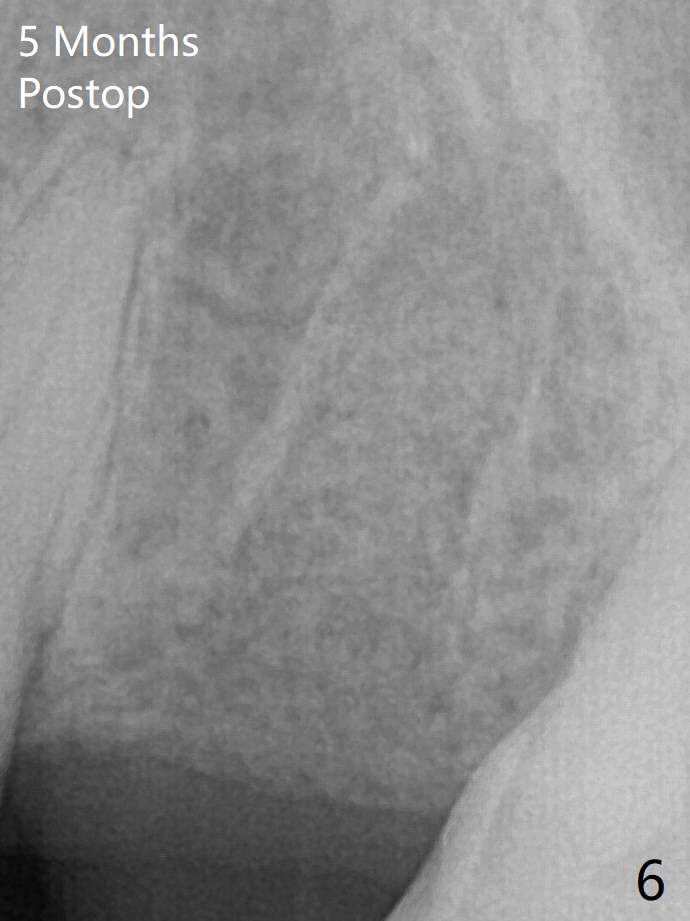

The coronal lamina dura becomes indistinct 5 months postop (Fig.6). The bone graft remains in the socket. There appears no bone graft loss. Great? Ready for implant placement? What is the next step?